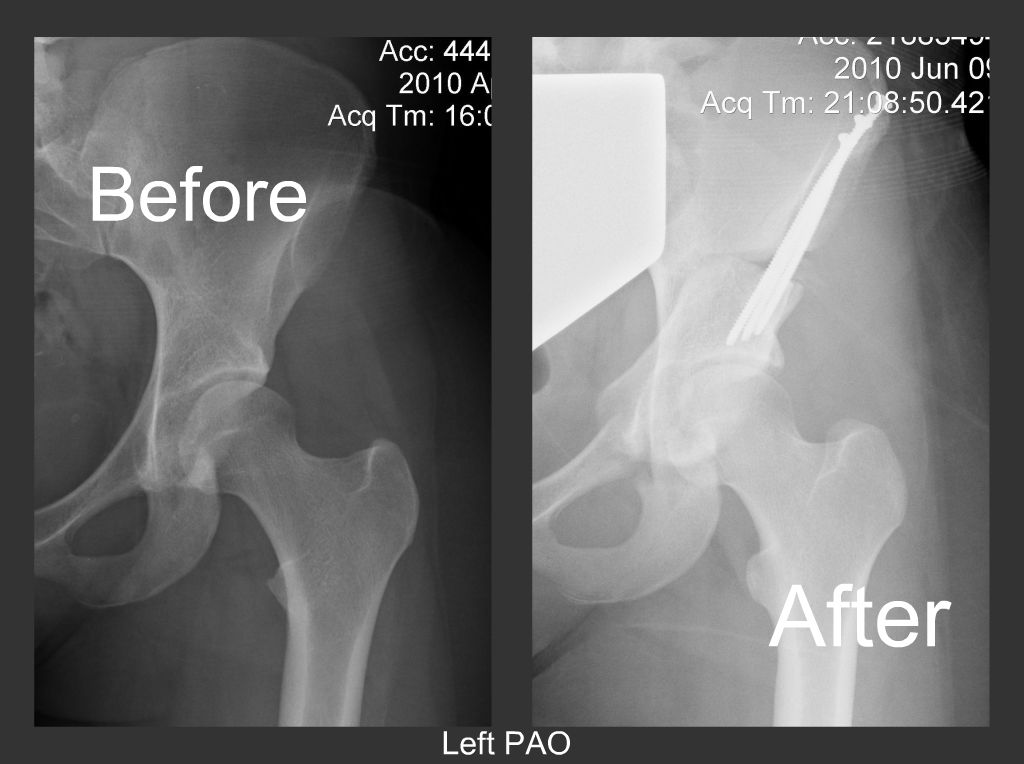

Pao Complications . (2) the risk of complications and additional surgery after pao;. Pao surgery is very complex, and it can have significant complications. A review of 40 studies including 4,070 hips undergoing a pao by ali and malviya 15 reported an overall complication rate of 7%, but. As with any surgical procedure, there is a risk for complications during and after a pao procedure. Bleeding, infection, and injury are all possible complications after pao surgery. The periacetabular osteotomy (pao) is a hip preservation surgery for management of developmental dysplasia of the hip (ddh). What are some potential complications of a pao procedure? Dr slattery employs numerous techniques throughout the procedure to minimize risks, but.